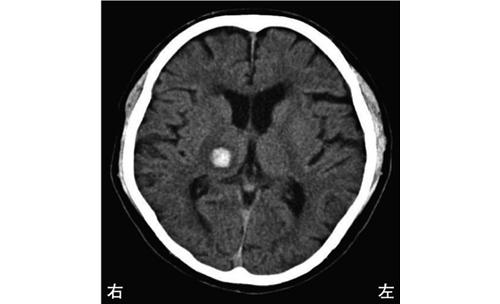

右内包後脚では、左上下肢の運動麻痺が見られるため、この選択肢は正しいです。